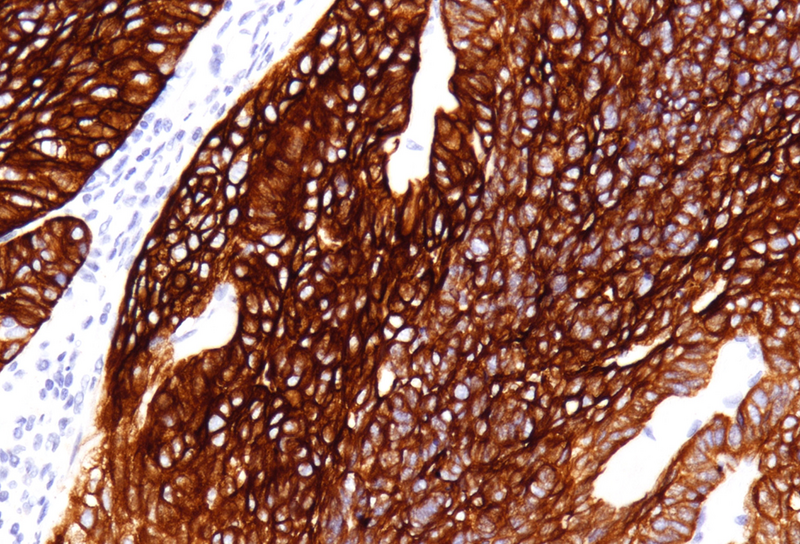

Immunohistochemistry revealed diffuse and strong cytoplasmic positivity for CK7 (Panel E) and CK19. Focal nuclear positivity was observed for p40 and p63 (Panel F). p16 immunostaining was diffusely positive, supporting a high-risk HPV-associated pathogenesis (Panel G). The tumor cells were negative for CK20, CK5/6, CDX2, synaptophysin, chromogranin, CD56, SOX10, PAX8, GATA3, TTF-1 and hormonal receptors. The Ki-67 proliferation index was markedly high (>90%) (Panel H). The immunohistochemical profile prompted a final diagnosis of poorly differentiated, presumably HVP-induced cancer originating from the ana glands, with a predominantly solid adenocarcinoma growth pattern yet minor squamous differentiation.